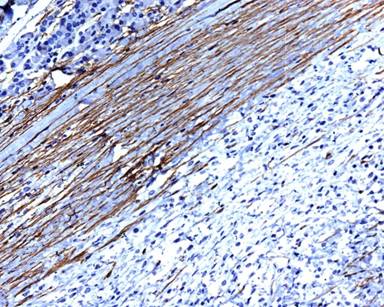

A 11-year-old male presented with complaints of painless hard swelling involving left lumber, umbilical and left hypochondrium of abdomen. According to his mother he was apparently asymptomatic 20 days back when he incidentally noticed firm to hard swelling in left upper abdomen. No history of fever, vomiting, jaundice, weight loss and hematemesis and bleeding per rectum was seen. No family history of a genetic disease was seen. Clinical examination was normal. Body fluid amylase was 4,800 U/L (reference range: 4-234 U/L) and liver function tests were normal. Computed tomography (CT) revealed a large mass measuring 10.0x8.8x7.5 cm in the pancreatic tail, mainly solid but small cystic component (Figure 1). The pancreatic tail mass was well-delimited but not encapsulated. There was no evidence of local invasion or metastasis. The surrounding vessels (celiac trunk, superior mesenteric artery, and splenic and portal veins) were not invaded. The surrounding pancreas was normal. The clinical diagnosis of adenocarcinoma of the pancreas was suspected. Resection of pancreatic tail mass and distal pancreatectomy with splenectomy was performed. Operative findings showed a mass with cyst involving pancreatic tail, adherent to splenic vein and artery, free from stomach and left kidney. The macroscopic examination revealed compressed pancreas measuring 4.0x1.0x0.5 cm, spleen measuring 8.5x6.0x3.5 cm with mesentery measuring 3.0x3.0x0.5 cm. and a well circumscribed, non-encapsulated, dense, mesenchymal tumor measuring 10.0x8.8x7.5 cm with a cystic area measuring 1.5 cm in diameter (Figure 2). Outer surface of the tumor was grey white and lobulated. No lymph node was seen. Histological examination showed a circumscribed tumor arranged in intersecting fascicles infiltrated the surrounding pancreatic parenchyma (Figure 3).Tumor cells are mildly anisomorphal with spindle shaped cells having elongated nuclei with blunt ends and bipolar cytoplasm. Mitosis is infrequent (less than 1-2 per 10 high power fields). Necrosis was not seen. Spindle shaped cells have a regular nucleus and were separated by large amounts of collagen fibers in edematous tissue with some inflammatory cells (Figure 4). The cystic component was seen within the tumor. Spleen showed congestion and focal fibrosis. Immunohistochemical analysis revealed that the tumor cells were strongly positive for beta-catenin (Figure 5), vimentin (Figure 6) and negative for cytokeratin (CK), CD34 (Figure 7), S100, CD68, CD117, smooth muscle actin (SMA) (Figure 8), muscle specific actin, desmin, CD99, Bcl2, anaplastic lymphoma kinase 1 (ALK-1) and human melanoma vlack 45. Proliferation marker Ki67 stained about 2% of the tumor cells. The immunohistochemistry and histopathological features were consistent with a confirmed diagnosis of desmoid tumor. A short term follow-up showed rapid disappearance of the symptoms which had revealed the desmoid tumor. Because of complete resection and the sporadic origin of the desmoid tumors, no corresponding treatment was given. After 10 months of follow-up, the patient is well and normal on clinical examination.

Figure 7. Tumor cells are negative for CD34 immunostaining (x40 magnification). |

Figure 8. Tumor cells are negative for smooth muscle actin (SMA) immunostaining (x40 magnification). |